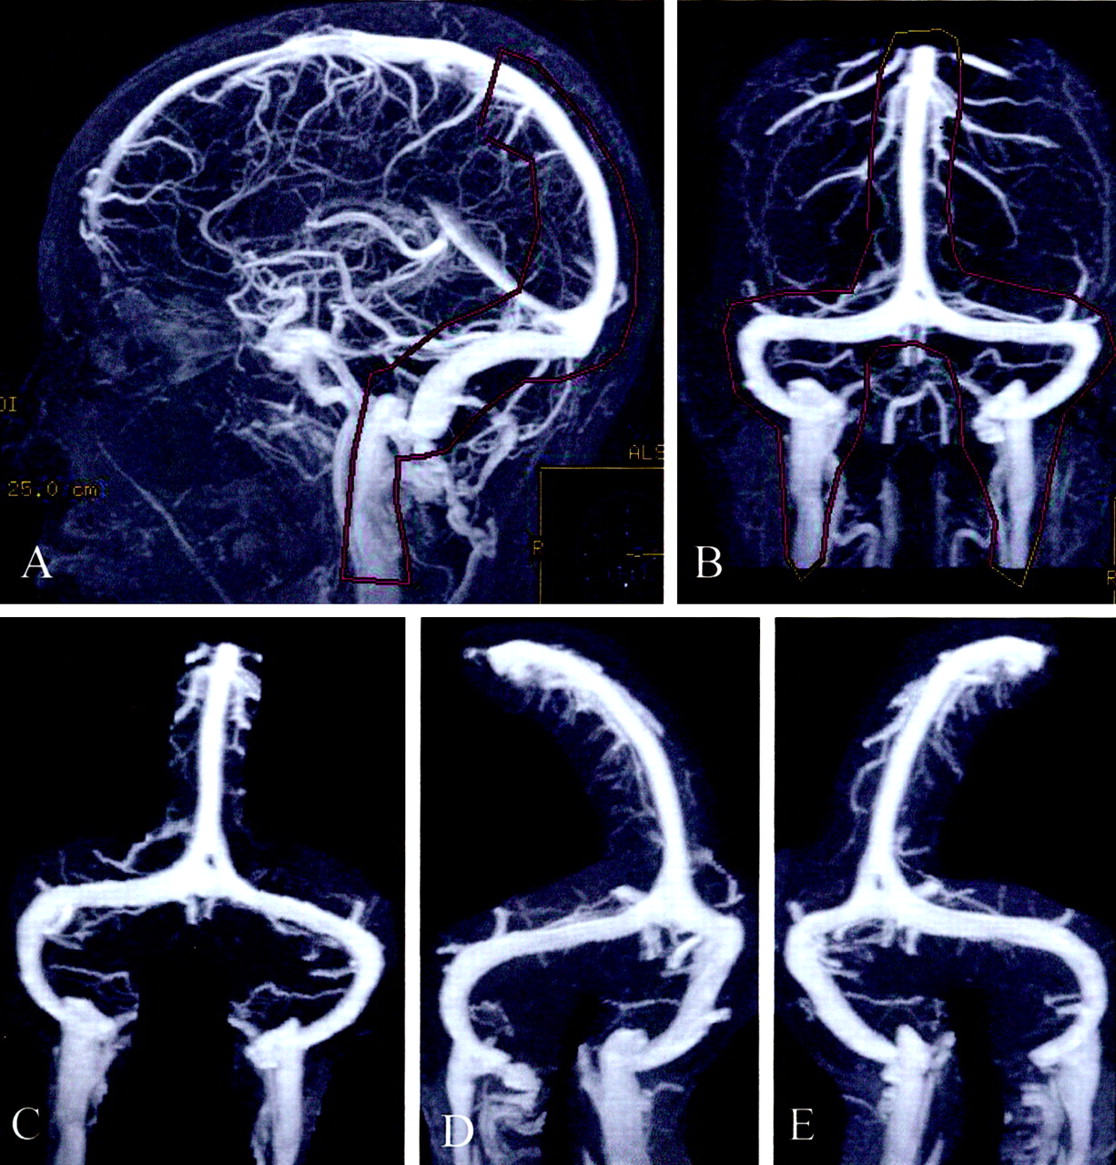

先生在过去的十年里,已经成为选择的形态检查静脉系统疑似患者颅内高压症排除静脉窦血栓形成。TOF血管造影术先生一直造影术先生的最受欢迎的技术到目前为止,尽管有局限性技术特别是artifactual信号的损失发生在静脉系统的可预测的位置由于平面流和湍流。6、16⇓具有讽刺意味的是,横在硬脑膜静脉窦和乙状窦的位置经常受到这样的工件(图6)。因此,与TOF MRV,远端横窦的重要地区通常会掩盖是否正常,狭窄的,或形成血栓。我们相信这陷阱早些时候MRV技术已经极大的混乱之源在试图定义MRV在颅内高压症的角色。17硬脑膜的鼻窦内的腔内狭窄的领域与颅内高压症无法欣赏到这里描述的一种新形式的造影术的发展,即ATECO MRV。ATECO血管造影术先生和造影术的技术已被证明是优于TOF技术在很大程度上由于其流不敏感和显著下降artifactual信号损失。6

图6。ATECO vs TOF MRV。(一)老挝和(B)拉奥分段最大强度投影(MIPs) ATECO MRV的控制病人展示良好的可视化的右(箭头)和左(打开箭头)横向和乙状窦。注意缺乏artifactual信号损失。(C和D)相应oblique-segmented MIPs从TOF MRV在同一病人获得先生在同一考试。注意信号的大量artifactual损失近端右横窦(弯曲的箭头)和最左横窦(箭头)。